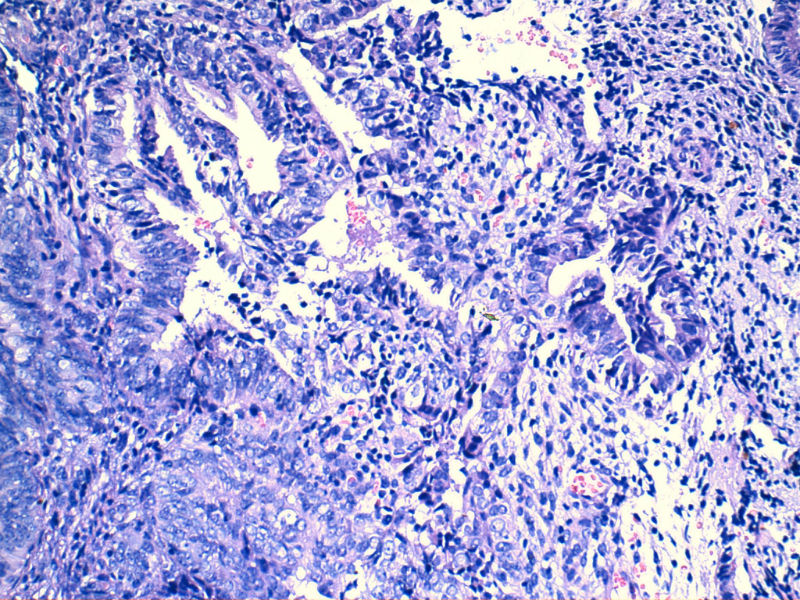

子宫内膜EIN?

图13是做为正常对照的,图7、8、9、12显示的核大小不一,空泡状,形状不规则。女,48岁,宫血半年

那一小块区域到复杂性非典型增生了。

局部腺体密集 复杂性增生

子宫内膜呈增生期改变伴局灶区域腺体密集核异性够EIN.